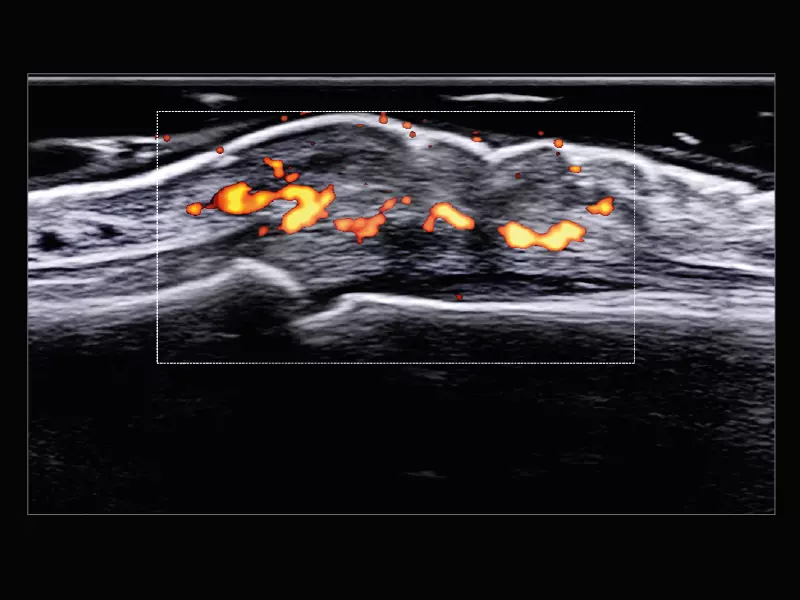

MyLab™9 Platform - Very-superficial linear imaging with Power Doppler algorithm

MyLab™9 Platform - Very-superficial linear imaging with Power Doppler algorithm